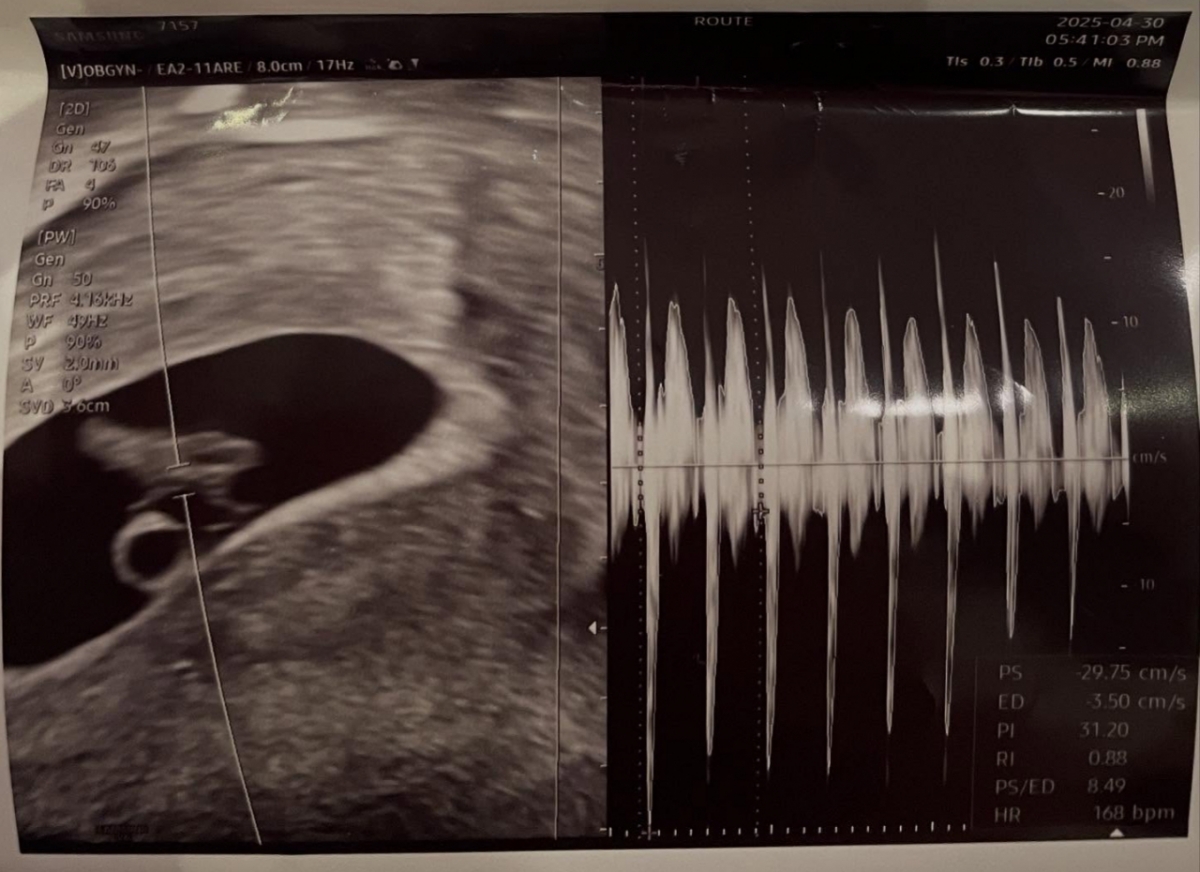

이어 "서씨는 임신 9주차에 접어드는 산모"라며 "심리적․정서적으로 절대적 안정을 취해야 함에도 정씨는 대형 법무법인을 선임해 서씨를 명예훼손, 감금, 스토킹으로 고소하겠다며 심리적 압박을 서슴지 않고 있다"고 지적했다.